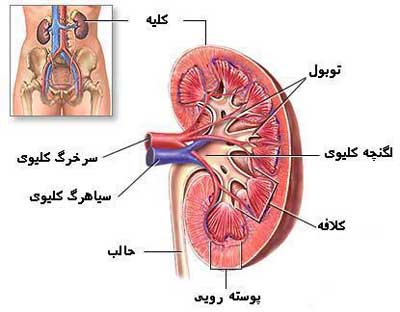

عکس کلیه در بدن. اگر پشت یا پهلوی شما آسیب ببیند مثل برخورد ضربه ممکن است فکر کنید که کلیه هایتان درد می کنند. مقدار و نسبت ترکیب این اخلاط در بدن هر شخصی و در اندامهای. کلیه گ رده ها1 از اندام های درونی بدن انسان به صورت یک جفت عضو لوبیایی شکل در طرفین ستون فقرات روی جدار پشتی شکم و بیرون از حفره صفاق قرار دارند. ک لیه ق لوه میز یا گ رده یکی از اندام های درونی بدن انسان و برخی دیگر از جانداران است.

در هر ساعت کلیه های بدن انسان حدود ۷ لیتر مایع را از خون جدا می کنند این مایع را تصفیه کرده و مواد مفید و سودمند آن را به خون بازمی گردانند و مواد مضر آن را از راه میزنای به مثانه می فرستد تا دفع شوند. کجای بدنتان درد می کند مراجعه کنید آیا کلیه تان درد می کند درد کلیه در اثر عفونت کلیه یا آسیب رسیدن به آن ایجاد می شود. اما کار و وظیفه کلیه ها در بدن چیست بیا یاد بگیریم. زمانیکه کلیه ها بدرستی فعالیت کنند مواد زائد از بدن داخل ادرار ترشح می شوند همچنین کلیه ها در تنظیم سایر مواد معدنی در بدن مانند.

کلسیم و فسفر که برای تشکلی استخوان لازمند کمک می کنند مواد. کلیه ها با تولید ادارد در دفع مواد زاید تعادل الکترولیتی تنظیم هورمونی تنظیم فشار خون و هوموستازگلوکز نقش دارند. آناتومی کلیه انسان در بدن انسان به این شکل است که کلیه ها دو عضو لوبیایی شکل در دستگاه ادراری بوده و به دفع مواد زائد به صورت ادرار کمک می کنند. یکی از مهم ترین وظایفی که کلیه ها در بدن بر عهده دارند پاک کردن و تصفیه خون از زباله هاست.